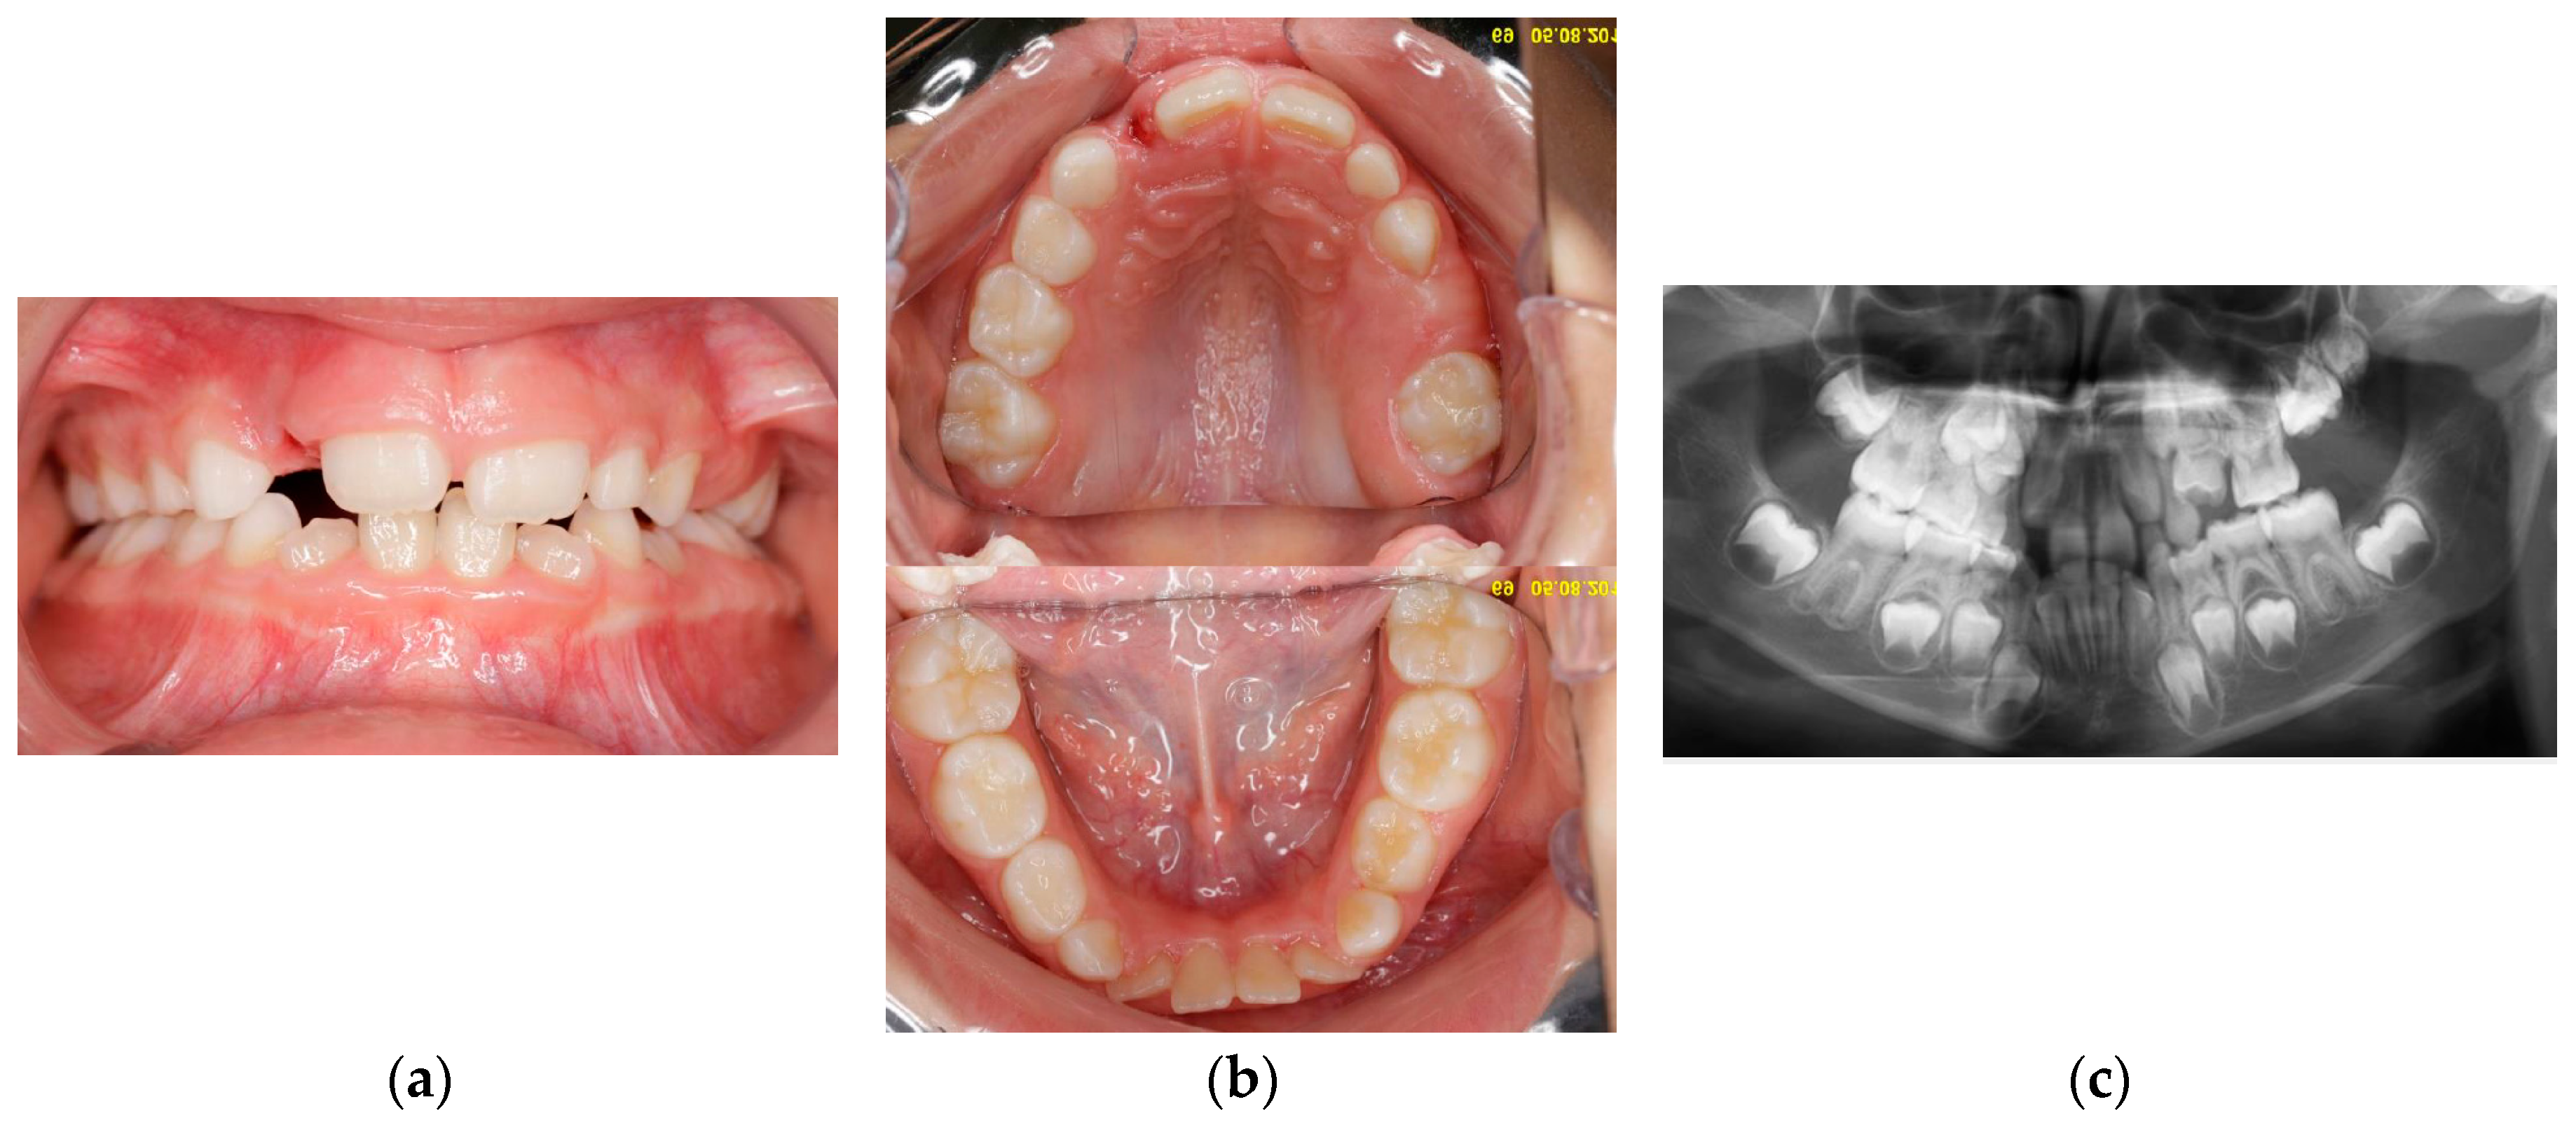

Eleven months later (age 5y 3m) a molar was erupting in the left upper arch. The erupting tooth was considered to be the second primary molar (65), although its shape and size as seen on the new panoramic X-ray substantially differed from those of 55, present on the arch. This new X-ray also suggested that 64 could be mechanically impacted by 63 (Figure 2a,b).

Four years later (age 7y 10m), 65 had fully erupted, with atypical crown shape and size (larger than usual, almost like a first permanent molar) (Figure 3a,b); no premolar buds could be seen in the upper left quadrant; unerupted 26 had reached the coronal stage, while 27 had a delayed development as compared to 17 (Figure 3c). 64 had become more re-intruded and seemed to be impacted by 63. PFE of upper left permanent molars was suspected. Some lower front crowding was also noticed.

Figure 2. Age 5 y 3 m: a) clinical view; b) Panoramic X-ray.